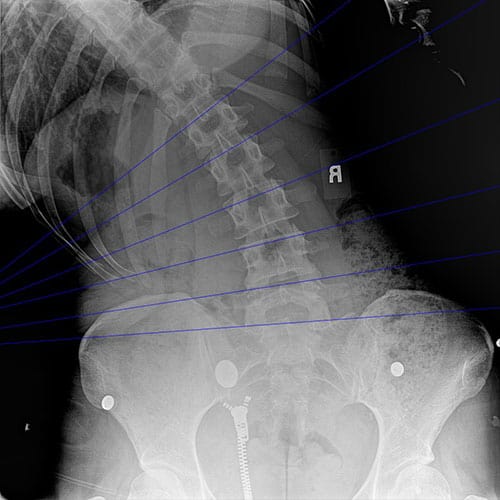

Normal AP lumbar

Normal Lat Bending